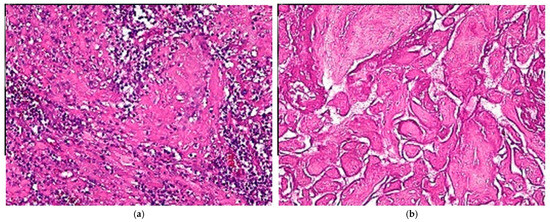

2. Case Presentation